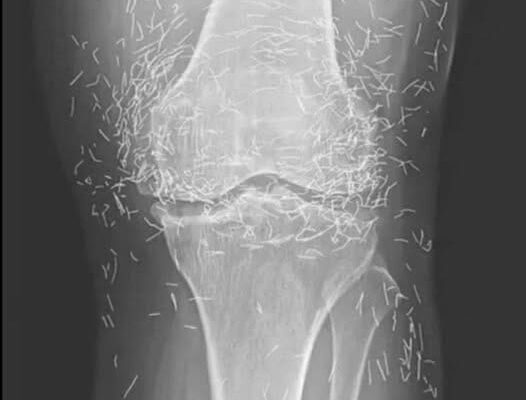

Years later, when doctors took X-rays to evaluate her knee condition, they weren’t prepared for what appeared on the images. Her knees were filled with dozens of bright, metallic flecks — tiny needles embedded deep within the joint area.

The findings were later documented in a case published by the New England Journal of Medicine.

Beyond inflammation, the needles created another problem: imaging complications. Metal objects can obscure parts of the anatomy on X-rays, making it harder for doctors to clearly assess joint damage or disease progression.

Even more concerning, the presence of metal inside the body can make certain scans dangerous. MRI machines rely on powerful magnetic fields, and embedded needles may shift during scanning, potentially damaging blood vessels or surrounding tissue. In short, future diagnostic options for this patient became limited.